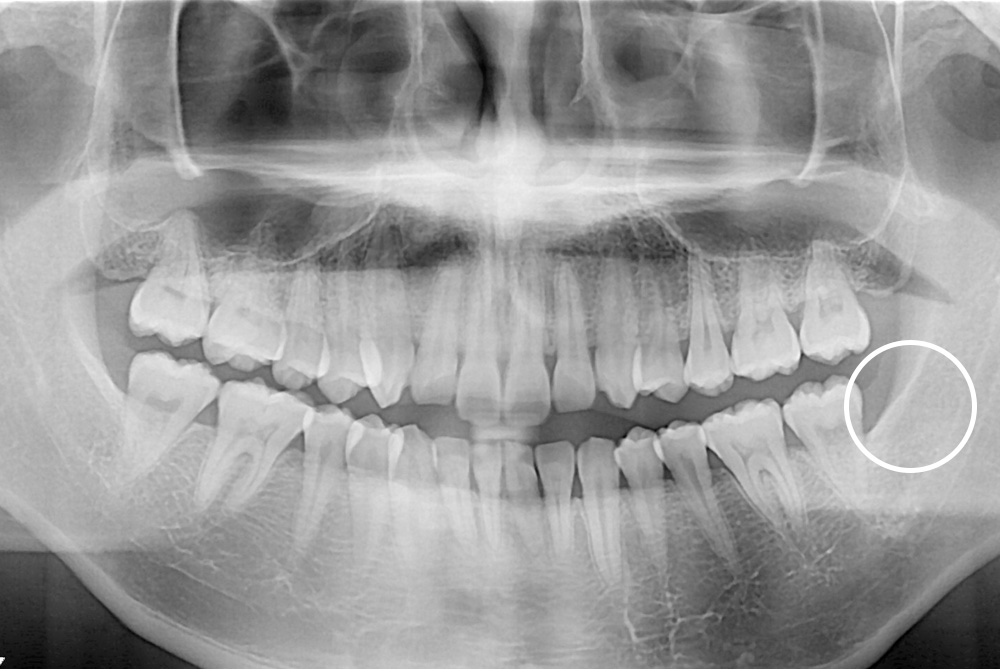

[사랑니] 매복 사랑니 발치

치료전 : 2019-02-11

세종치과는 구강악안면외과학 박사이신 원장님이 발치하는 치과입니다.